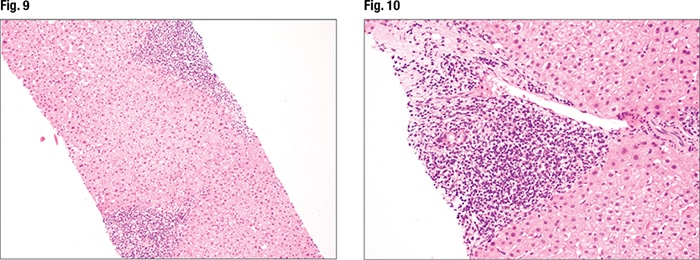

[dropcap]I[/dropcap]n Fig. 7 is an image from a second case. “This is an adequate biopsy,” Dr. Pezhouh said. “I have at least three cores of liver; they seem long, they don’t seem fragmented.” There is inflammation and it appears to be in the portal tracts. The lobular inflammation looks slightly dispersed, “but at this power it’s hard to see lobular activity.” At slightly higher power (Figs. 8 and 9), “again I see inflammation in the portal tracts but not much in the lobules. The portal tracts [right and left sides of liver core] are expanded by inflammation.” On higher power (Fig. 10) there are areas that show bile duct injury. Lymphocytes are rimming around and in between bile duct epithelium, causing bile duct injury, she said, indicating an irregular bile duct (mid-left). Another bile duct (Fig. 11, center) looks rounder, “but still you see lymphocytes in between the epithelium and it doesn’t look happy; it’s a little pinkish.” It seems that bile ductitis is present.